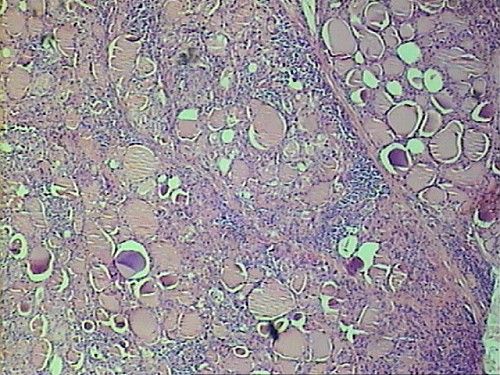

This thyroid shows scattered foci of dense lymphocyte infiltration. Note that thyroid follicles are in normal size (Fig.1).

Germinal center (secodary lymphoid follicles) may present in some of the lymphoid infiltration (Fig.2).

The lymphoid infiltration causes destruction and cellular change to the follicular cells within the area. The altered follicular cells may show enlarged nuclei and increase of eosinophilic granular cytoplasm (Fig.3).

This change is called oncocytic or Hurthle cell change. Compare the oncocytic follicular cells to normal follicular cells (Fig.4)( This change alone is not pathognomonic and can occur in various conditions).